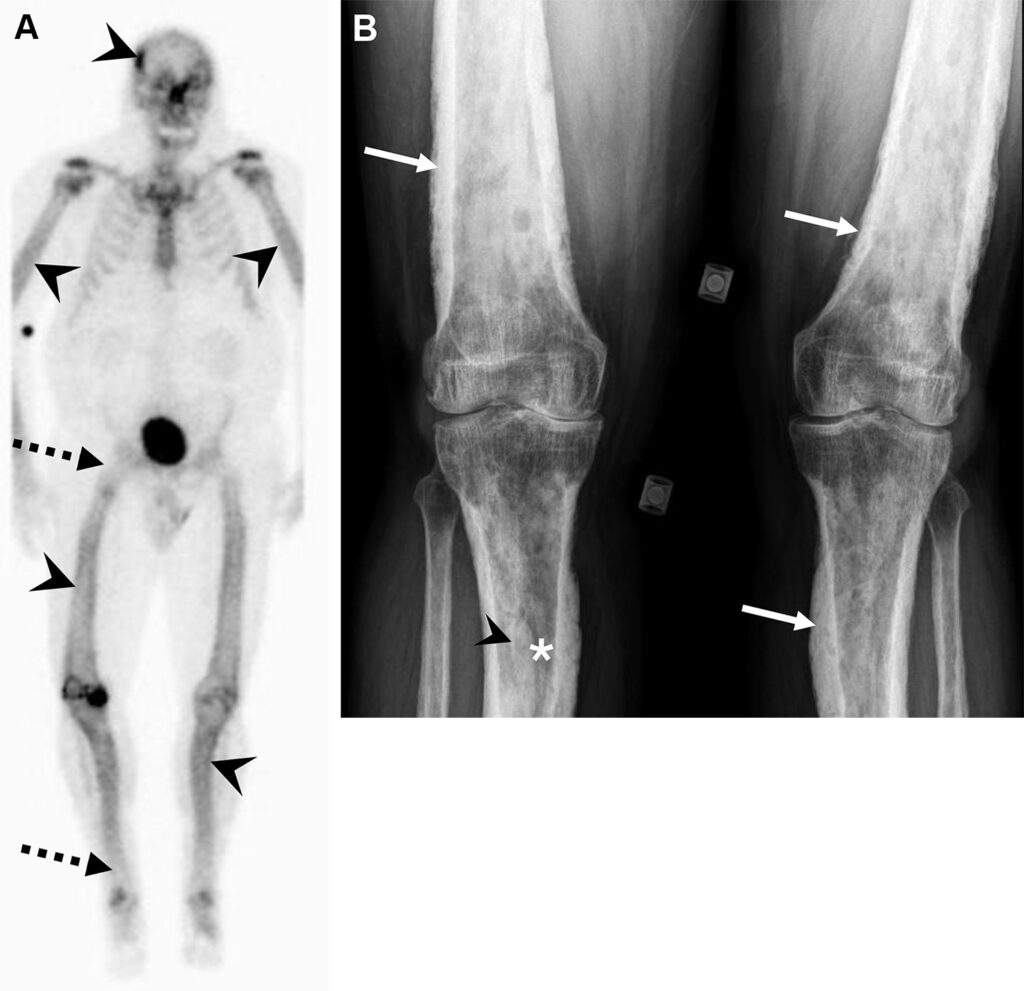

Malattia di Erdheim-Chester in un uomo di 47 anni con dolore osseo aspecifico.

La scintigrafia ossea whole-body evidenzia un’intensa ipercaptazione simmetrica e confluente a carico delle ossa lunghe (in particolare distretto dia-metafisario ed epifisario di ginocchia e caviglie). Come reperto incidentale, si osserva un ristagno di tracciante nel rene destro, indice di ostruzione delle vie urinarie.

La TC conferma una marcata osteosclerosi nelle medesime sedi ipercaptanti e la presenza di una massa tissutale infiltrante che avvolge simmetricamente i reni (aspetto a “cercine” o hairy kidney) e infiltra il mesentere. Questa fibrosi retroperitoneale spiega l’ostruzione dell’efflusso renale destro rilevata in scintigrafia.

La malattia di Erdheim-Chester è una rara istiocitosi non-Langerhans caratterizzata da una proliferazione sistemica di macrofagi. Il pattern di osteosclerosi simmetrica dia-metafisaria bilaterale delle ossa lunghe, associato all’infiltrazione perirenale, è considerato un quadro radiologico quasi patognomonico per questa patologia.